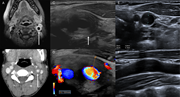

Figure 1. Imaging of perivascular inflammation of the left internal carotid artery at diagnosis and at 4 wk of treatment. (A–F) At diagnosis: circumferential parietal thickening (white arrows) of the left carotid artery wall on axial cervical More about this image found in Imaging of perivascular inflammation of the left internal carotid artery at...